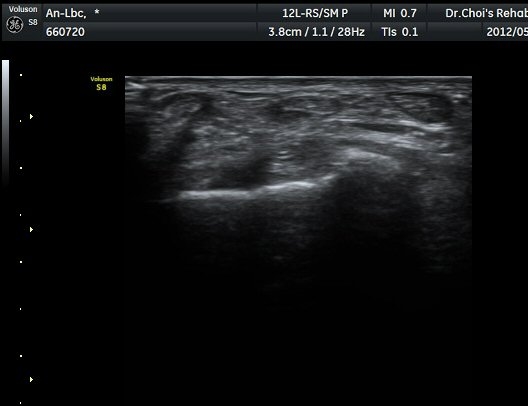

¹ß¸ñ ¾Õ Ⱦ´Ü¸é°Ë»ç¿¡¼­ Àü°æ°Ç(TA), ¾öÁö½ÅÀü°Ç(EPL), ¹ß°¡¶ô½ÅÀü°Ç(EDL)ÀÇ ºÎÁ¾ ¹×

°Ç ÁÖÀ§ ¼ö¾× Àú·ù°¡ °üÂûµÈ´Ù(»çÁø 1, 2). °ÇÀÇ ºñÈÄ¿Í ¼ö¾×Àú·ù´Â °ÇÃø(»çÁø 4)°ú ºñ±³Çϸé

¶Ñ·ÈÇÏ´Ù. Àü°æ°Ç Á¾´Ü¸é°Ë»ç¿¡¼­ °ÇÀÇ ºÎÁ¾°ú °Ç ÁÖÀ§ ¼ö¾× Àú·ù°¡ °üÂûµÈ´Ù(»çÁø 3). °ÇÀÇ

ºÎÁ¾°ú ¼ö¾×Àú·ù´Â °ÇÃø°ú ºñ±³ÇÏ¸é ¶Ñ·ÈÇÏ´Ù(»çÁø 5).¤·